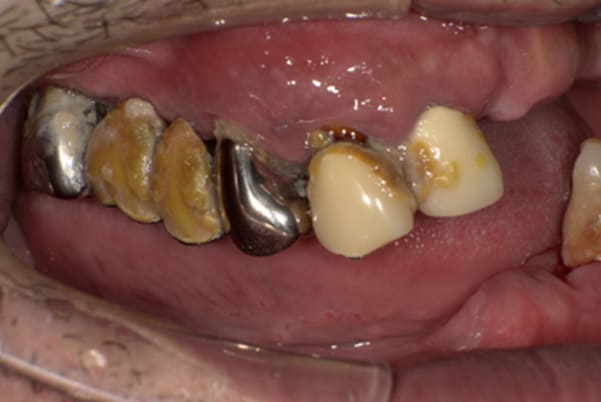

症例レポート[CASE.02]

- 男性(60代)

- 入れ歯がカパカパする、歯がぐらぐらして痛い、食いしばれない

- 治療

- 上顎精密総金属床総入れ歯

- 下顎精密金属床部分入れ歯

- ジルコニアクラウン4歯

- 治療期間

- 約3か月間

- 費用

- 上顎精密総金属床総入れ歯:55万円

- 下顎精密金属床部分入れ歯:55万円

(ミリング、ラベット加工込み) - ジルコニアクラウン:11万円×4歯

合計:154万円(税込)

上の前歯が重度歯周病により動揺し、残せない状態のため、入れ歯も動揺がありました。

ご自身の歯に負担の少ないバネ、また見た目も改善

銀歯からセラミック歯に

バネをかける歯は繋げることで強度を増し、歯への負担を軽減し、歯の寿命を長くする設計へ。

バネがかかる歯の被せ物は、歯への負担を減らし、入れ歯が動きにくいようになる形態をあらかじめ付与することで、より入れ歯の機能が高まります。

治療を行う際、被せ物や入れ歯は、別々に考えるのではなく、一口腔単位としてお口全体のことを考え最良の治療計画を立てることが歯の寿命、機能効果を向上させるため、専門医としてこのことは常に心掛けて治療を行っています。

治療前は上下奥歯の入れ歯が削れていることで、かみ合わせが低くなり唇もつむった状態でした。

かみ合わせを適切な高さに戻したことで、本来の自然な口元へ。